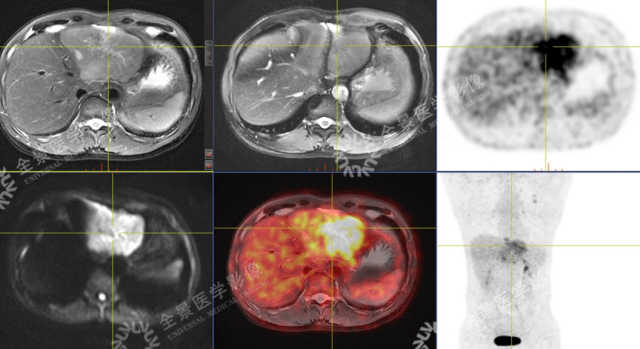

男 50 岁 小肝癌:

案例一